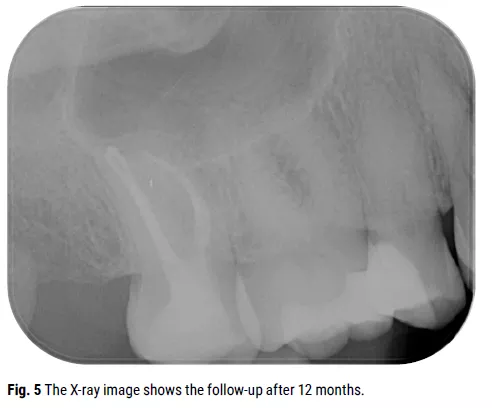

In the second appointment, final preparation was completed with the Traverse glide path 13/.06 file and ZenFlex files: MB1 40/.06, MB2 25/.06 (prepared only to the connection), DB 40/.06, and P 40/.06. Copious NaOCl irrigation and activation of the solution were repeated at each stage. NaOCl was removed and EDTA was left in the root canal system for 5 minutes. NaOCl was used as the final irrigant. A single-cone obturation technique was performed using a calcium-silicate-based sealer. Core build-up with short-fiber reinforced composite was applied, followed by a top layer of composite to restore the correct occlusal morphology. A final intraoral X-ray was taken post-treatment (Fig. 4). The patient was scheduled for a 12-month recall (Fig. 5).